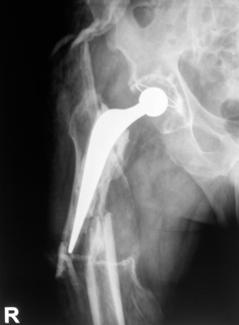

Pacientii inclusi in aceasta lucrare au fost protezati cu unul din urmatoarele tipuri de proteza: Exeter - Stryker Corp. , DLS (distal locking stem) - Stryker Corp. si proteze modulare.

Proteza Exeter.

Este o proteza neteda, impactata ce realizeaza o distributie circulara a fortelor exercitate la nivelul articulatiei soldului si care reduce forta de frecare intre proteza si os pe masura ce proteza migreaza distal. Rata de decimentare aseptica declarata de producator a fost de 0,5% la 13 - 18 ani de la implantare. Spre deosebire de protezele cu suprafata mata, proteza Exeter a realizat migrarea catre distal numai la nivelul interfetei proteza - ciment, astfel mentinand nealterata fixarea la nivelul interfetei ciment - os.

Pentru a asigura o buna implantare a protezei se folosesc centralizatoare care permit protezei sa migreze spre distal in interiorul mansonului de ciment, reducand stress-ul de la acest nivel si astfel crescand durata de supravietuire a protezei. Se pot folosi doua tipuri de centralizatoare, cu sau fara aripioare.

Fiind o proteza cimentata, se introduce in maniera descrisa in cadrul tratamentului decimentarii aseptice, continut in partea generala a lucrarii.

Protezele sunt disponibile intr-o gama larga avand:

- capete - din aliaj - 22, 26, 28, 30, 32, 36 (mm);

- din material ceramic - 28, 32, 36 (mm);

- offset-uri - 30, 32, 35,5, 37,5, 44 (mm);

- lungimi - 130, 150, 200, 205, 220, 240, 260 (mm).